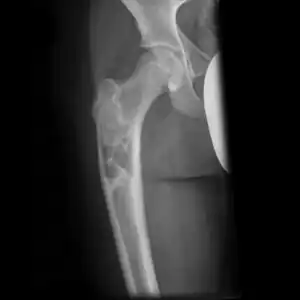

Simple bone cysts are often found incidentally on X-rays. About 90 to 95% of the lesion is found in metaphysics of long bones. The cyst is centered, oblong in shape along the long axis of a long bone. Rarely, they are large and multicameral and are found in diaphysis. When fracture is present, there may be a small bone fragment migrated in the cystic fluid. This is called "fallen fragment sign" which is diagnostic of simple bone cyst. Besides, a bubble migrating upwards (known as "rising bubble sign") is another feature suggesting of simple bone cyst.[7]

Multloculated cavity in the long bone of the thigh, near the hip. -

Break through simple bone cyst in the long bone of the thigh, near the hip.